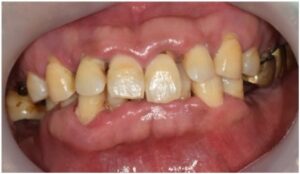

식립해 둔 임플란트가

단단히 결합되기를 기다리는 동안

위아래 앞니 브릿지 보철물 수복을 위한

치아 다듬기를 진행하였으며,

발치 부위의 잇몸이 아물기 전까지

임시치아를 사용하실 수 있도록

도와드렸습니다.

앞니 임시치아에 맞춰

임시틀니를 제작하여

환자분의 무너진 교합 고경을 맞춰드리는

작업을 진행하였는데요.